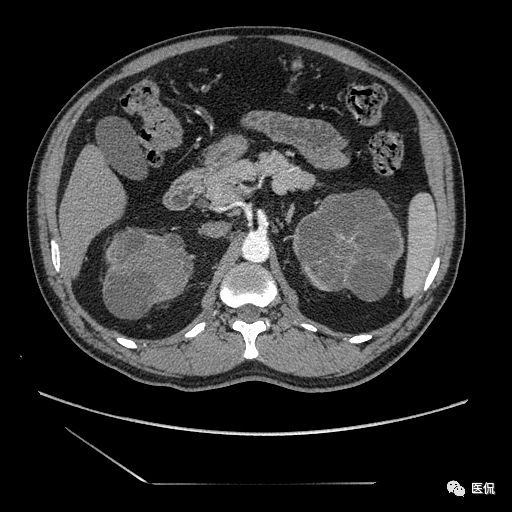

双肾实质可见多发囊性密度灶,其内密度不均匀,并可见钙化灶,增强扫描未见明显强化灶。肾周脂肪间隙清晰,与邻近组织分界清楚。

多囊肾的 CT 表现主要表现为双肾增大,轮廓光滑或有分叶,肾实质内多个大小不等的囊肿呈蜂窝状,多呈水样低密度,增强扫描囊肿本身无强化,而囊肿间正常肾组织增强,对比明显。当囊肿张力过高,使囊壁上毛细血管牵拉破裂出血时,表现为囊肿内稍高密度影,随访CT 值减低。囊壁钙化,表现为点线状高密度影像,随访CT值无变化。有文献报道约 30%病例可并发多囊肝或多囊胰。